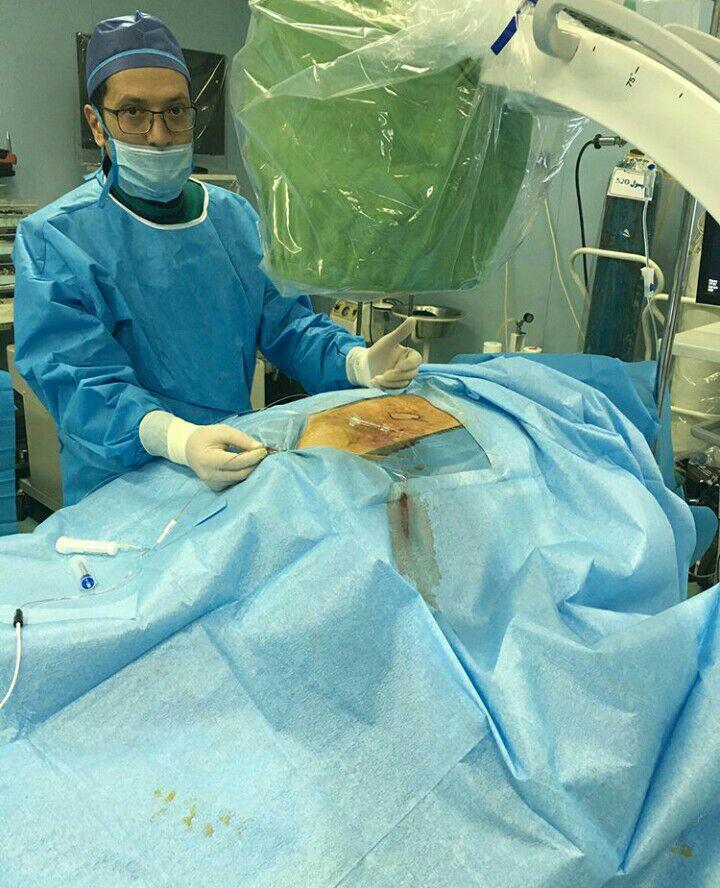

دکتر سعیدرضا انتظاری در تهران

دکتر سعیدرضا انتظاری در تهران

فلوشیپ اینترونشنال درد (فوق تخصص درد)

استادیار دانشگاه علوم پزشکی ایران , عضو انجمن جهانی درد

-لیزر(جراحی بسته) دیسک کمری